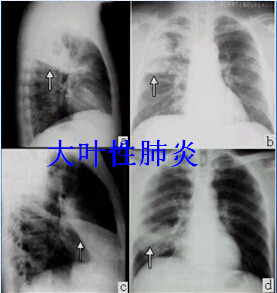

肺炎球菌肺炎:

早期仅见肺纹理增粗或受累的肺段、肺叶稍模糊。近年由于抗生素的应用,典型的大叶实变少见。实变阴影中可见支气管气道征,肋膈角可有少量胸腔积液征。肺炎消散期,X线浸润逐渐吸收,可有片块区域吸收较早,呈现“假空洞”征。